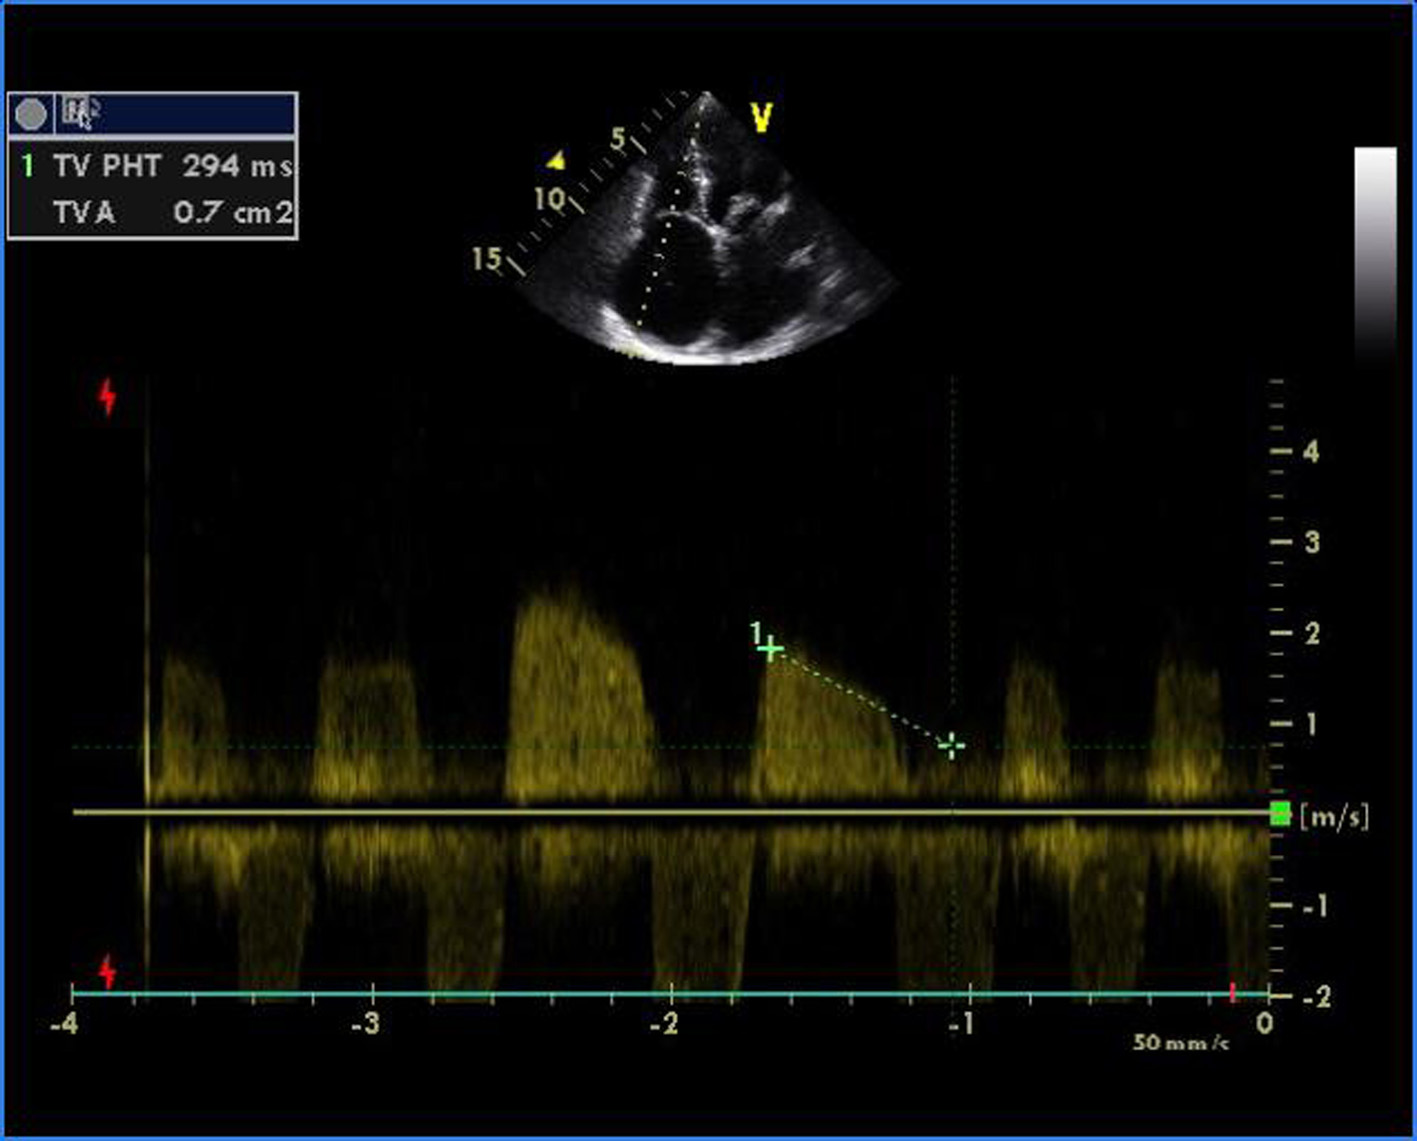

Figure 1. Transthoracic echocardiogram of apical four-chamber view showing thickened and doming mitral valve and tricuspid valve.

Malignant Rheumatic Heart Disease Presenting as Quadrivalvular Stenosis